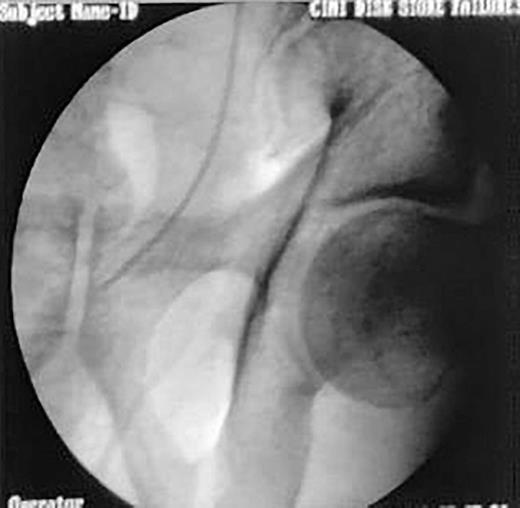

With considerable curiosity, we have read a recent article by Korkes and associates [1]. The article’s focus was on the medical management of stent-related symptoms, specifically the use of alpha antagonists, antimuscarinics, and PDE inhibitors either separately or in combination to lessen the symptoms associated with stents. The distal end of the DJ stent is known to cause pain and voiding symptoms, which is one of the causes contributing to stent-related symptoms [2]. Symptoms can be greatly reduced with a small modification to the ureteral stent. The traditional DJ stent’s lower coil is cut, and its lower end is stitched with a 5-0 mersilk (Fig. 1). Having placed it under fluoroscopy supervision (Fig. 2), we then bring the suture beyond the urethra and sew it to the labia majora in females and the glans penis in males (Fig. 3). We ask the patient to come to the outpatient department on the day of the stent removal. In the office environment itself, we cut the thread and pull the stent together with the thread under all hygienic circumstances. This method can greatly lessen the symptoms associated with the stent while also saving the patient a great deal of money and time. The evidence in favor of our position comes from a trial [3] in which the DJ stent’s distal coil was taken out for a custom-made distal coil that had a 0.3 Fr suture that reached the bladder and shown lower SRS and improved tolerance.